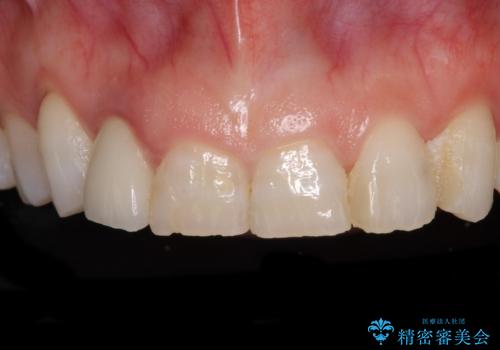

歯肉が腫れている前歯 外科処置を併用したオールセラミッククラウン

- 前歯のクラウン周りに歯肉が腫れていることを気にして来院された患者様です。

元々磨き残しによる歯肉の腫脹がありましたが、クラウンが歯肉深くに装着されていたため、特に腫脹が目立っていました。

仮歯に置き換えた際に歯周外科処置を行い、歯肉の腫脹が落ち着いたことを確認してオールセラミッククラウンにて補綴することとしました。

気になっていた腫脹がなくなり、患者様には大変満足していただきました。